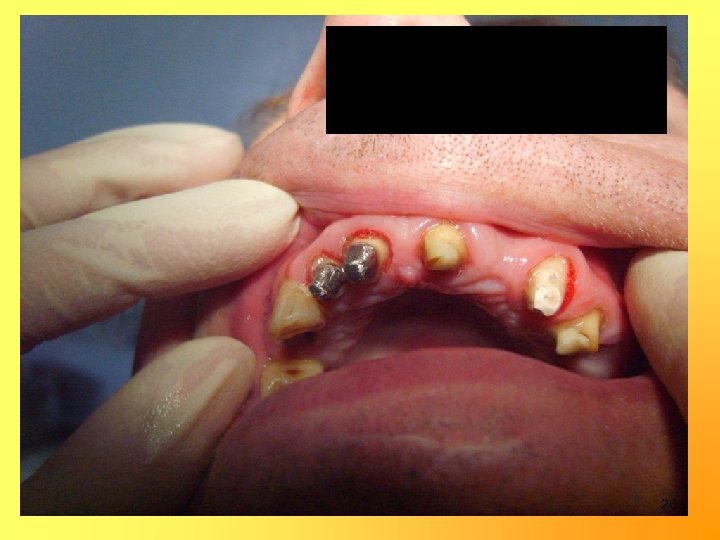

Изготовление металлокерамических мостовидных протезов и коронок 1, 5 -2, 0 мм 1, 0 -1, 5 мм 1, 0 мм 24

25

Изготовление временных коронок на 15, 13, 12, 11, 23, 24, 43 27